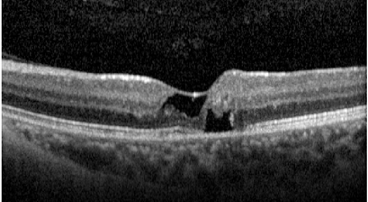

A telangiectasia macular é uma anormalidade dos capilares foveais e perifoveais associada à perda das camadas nucleares externas e da zona elipsoide, podendo progredir para lesões císticas (cavitações).

O OCT mostra fluido subretiano, com descolamento do epitélio pigmentar (DEP) em formato de “M”, sugestivo de vasculopatia polipoidal